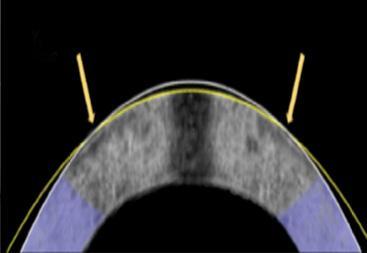

电流重塑角膜技术能有效矫正视力